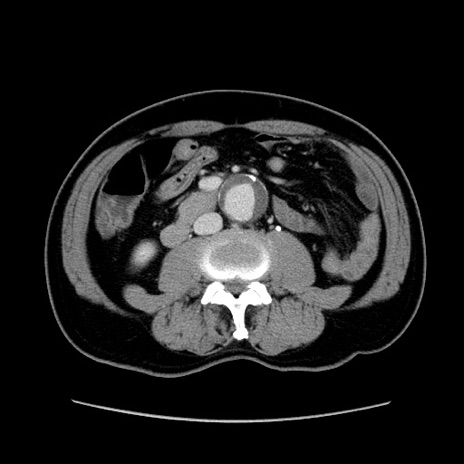

症例34(横断像)

【症例】60歳代 男性

【主訴】右鼠径部膨隆

【現病歴】1年程前より右鼠径部膨隆あり。自己にて還納可能だったため放置していた。3時間前より右鼠径部の脱出を認め、還納困難となり受診。

【身体所見】右鼠径部に小児頭大の膨隆あり。弾性硬であり、用手還納は困難。左鼠径部にも膨隆を認める。脱出はなし。